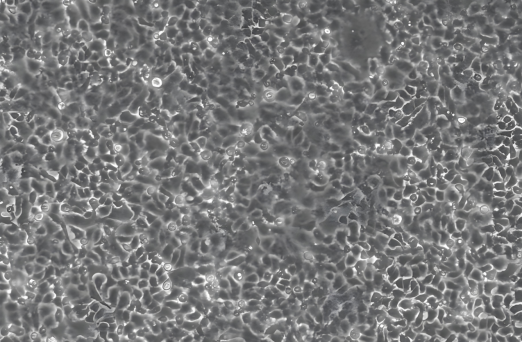

4、病毒辅助分析:通过细胞培养观察病毒引起的细胞病变效应(CPE)。

3、推荐倒置生物显微镜MI52-N/MIX60+明美显微相机MD60/MDX10,适用于病毒辅助观察。

倒置生物显微镜MI52-N:采用无穷远独立消色差光学,标配平场半复消色差物镜、10X/22大视场目镜,搭配长寿命高亮度的相衬LED光源,实现在明场和相衬下均可获得好的成像。

研究级生物显微镜MIX60:成像高性能,使用智能化,超长工作距离聚光镜,支持明场和相差观察,可升级拓展荧光观察。配备OLED数显屏幕和语音播报功能,实时显示光强和物镜倍率。